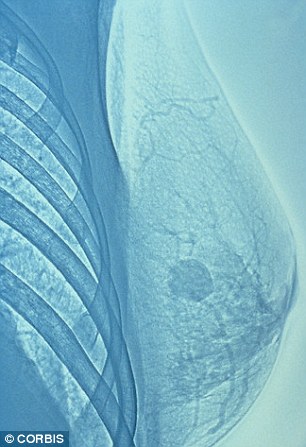

Эссекс, Сомерсэт дэх АЦС-уудын ойр хавьд хөхний хорт хавдрын өвчлөл үндэсний дунджаас өндөр байна. Хөхний хорт хавдрын зураг.